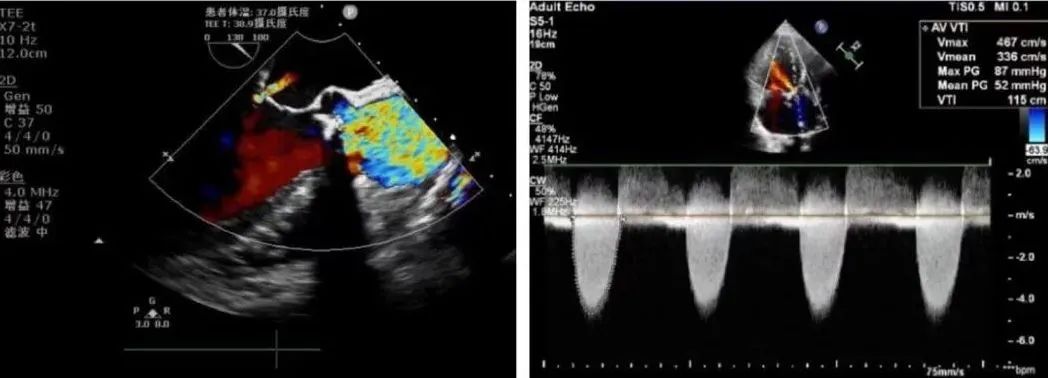

最后,行升主动脉成形关闭主动脉切口,停机,撤除体外循环,止血后关闭手术切口,手术切口约5cm(图17,18)。

图19,20